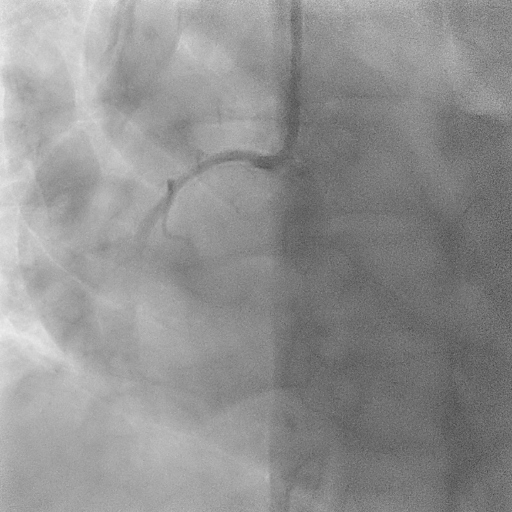

The coronary angiogram showed a right-dominant system. The right coronary artery (RCA) had a patent mid stent with mild diffuse disease and good TIMI 3 flow. The Quantitative Flow Ratio (QFR) was 0.97, indicating preserved physiological flow. A dual LAD anatomy was noted with significant bifurcation lesions (Medina 1,1,1) involving the mid first LAD and the ostial to mid second LAD. The non-dominant left circumflex artery and left main stem were normal.